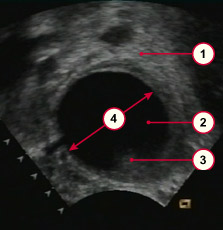

Созревание фолликула в яичнике: этапы и процессы